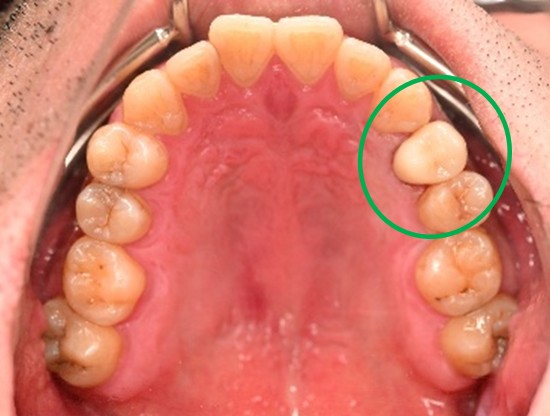

女性 Aさん 50代 (セラミックインレー)

主訴

左上の銀歯2本を白くしたい。

治療内容

銀歯を取り除き、セラミックインレーをいれました。

所感

患者さんは、お口の中の金属を徐々に取り除くことを希望され、今回は左上の奥歯2本をセラミックに替え、ノンメタルにしました。体全体の健康を考えると正しい選択だと思います。

セラミックインレー2本:¥52,800×2本=¥105,600(税込)